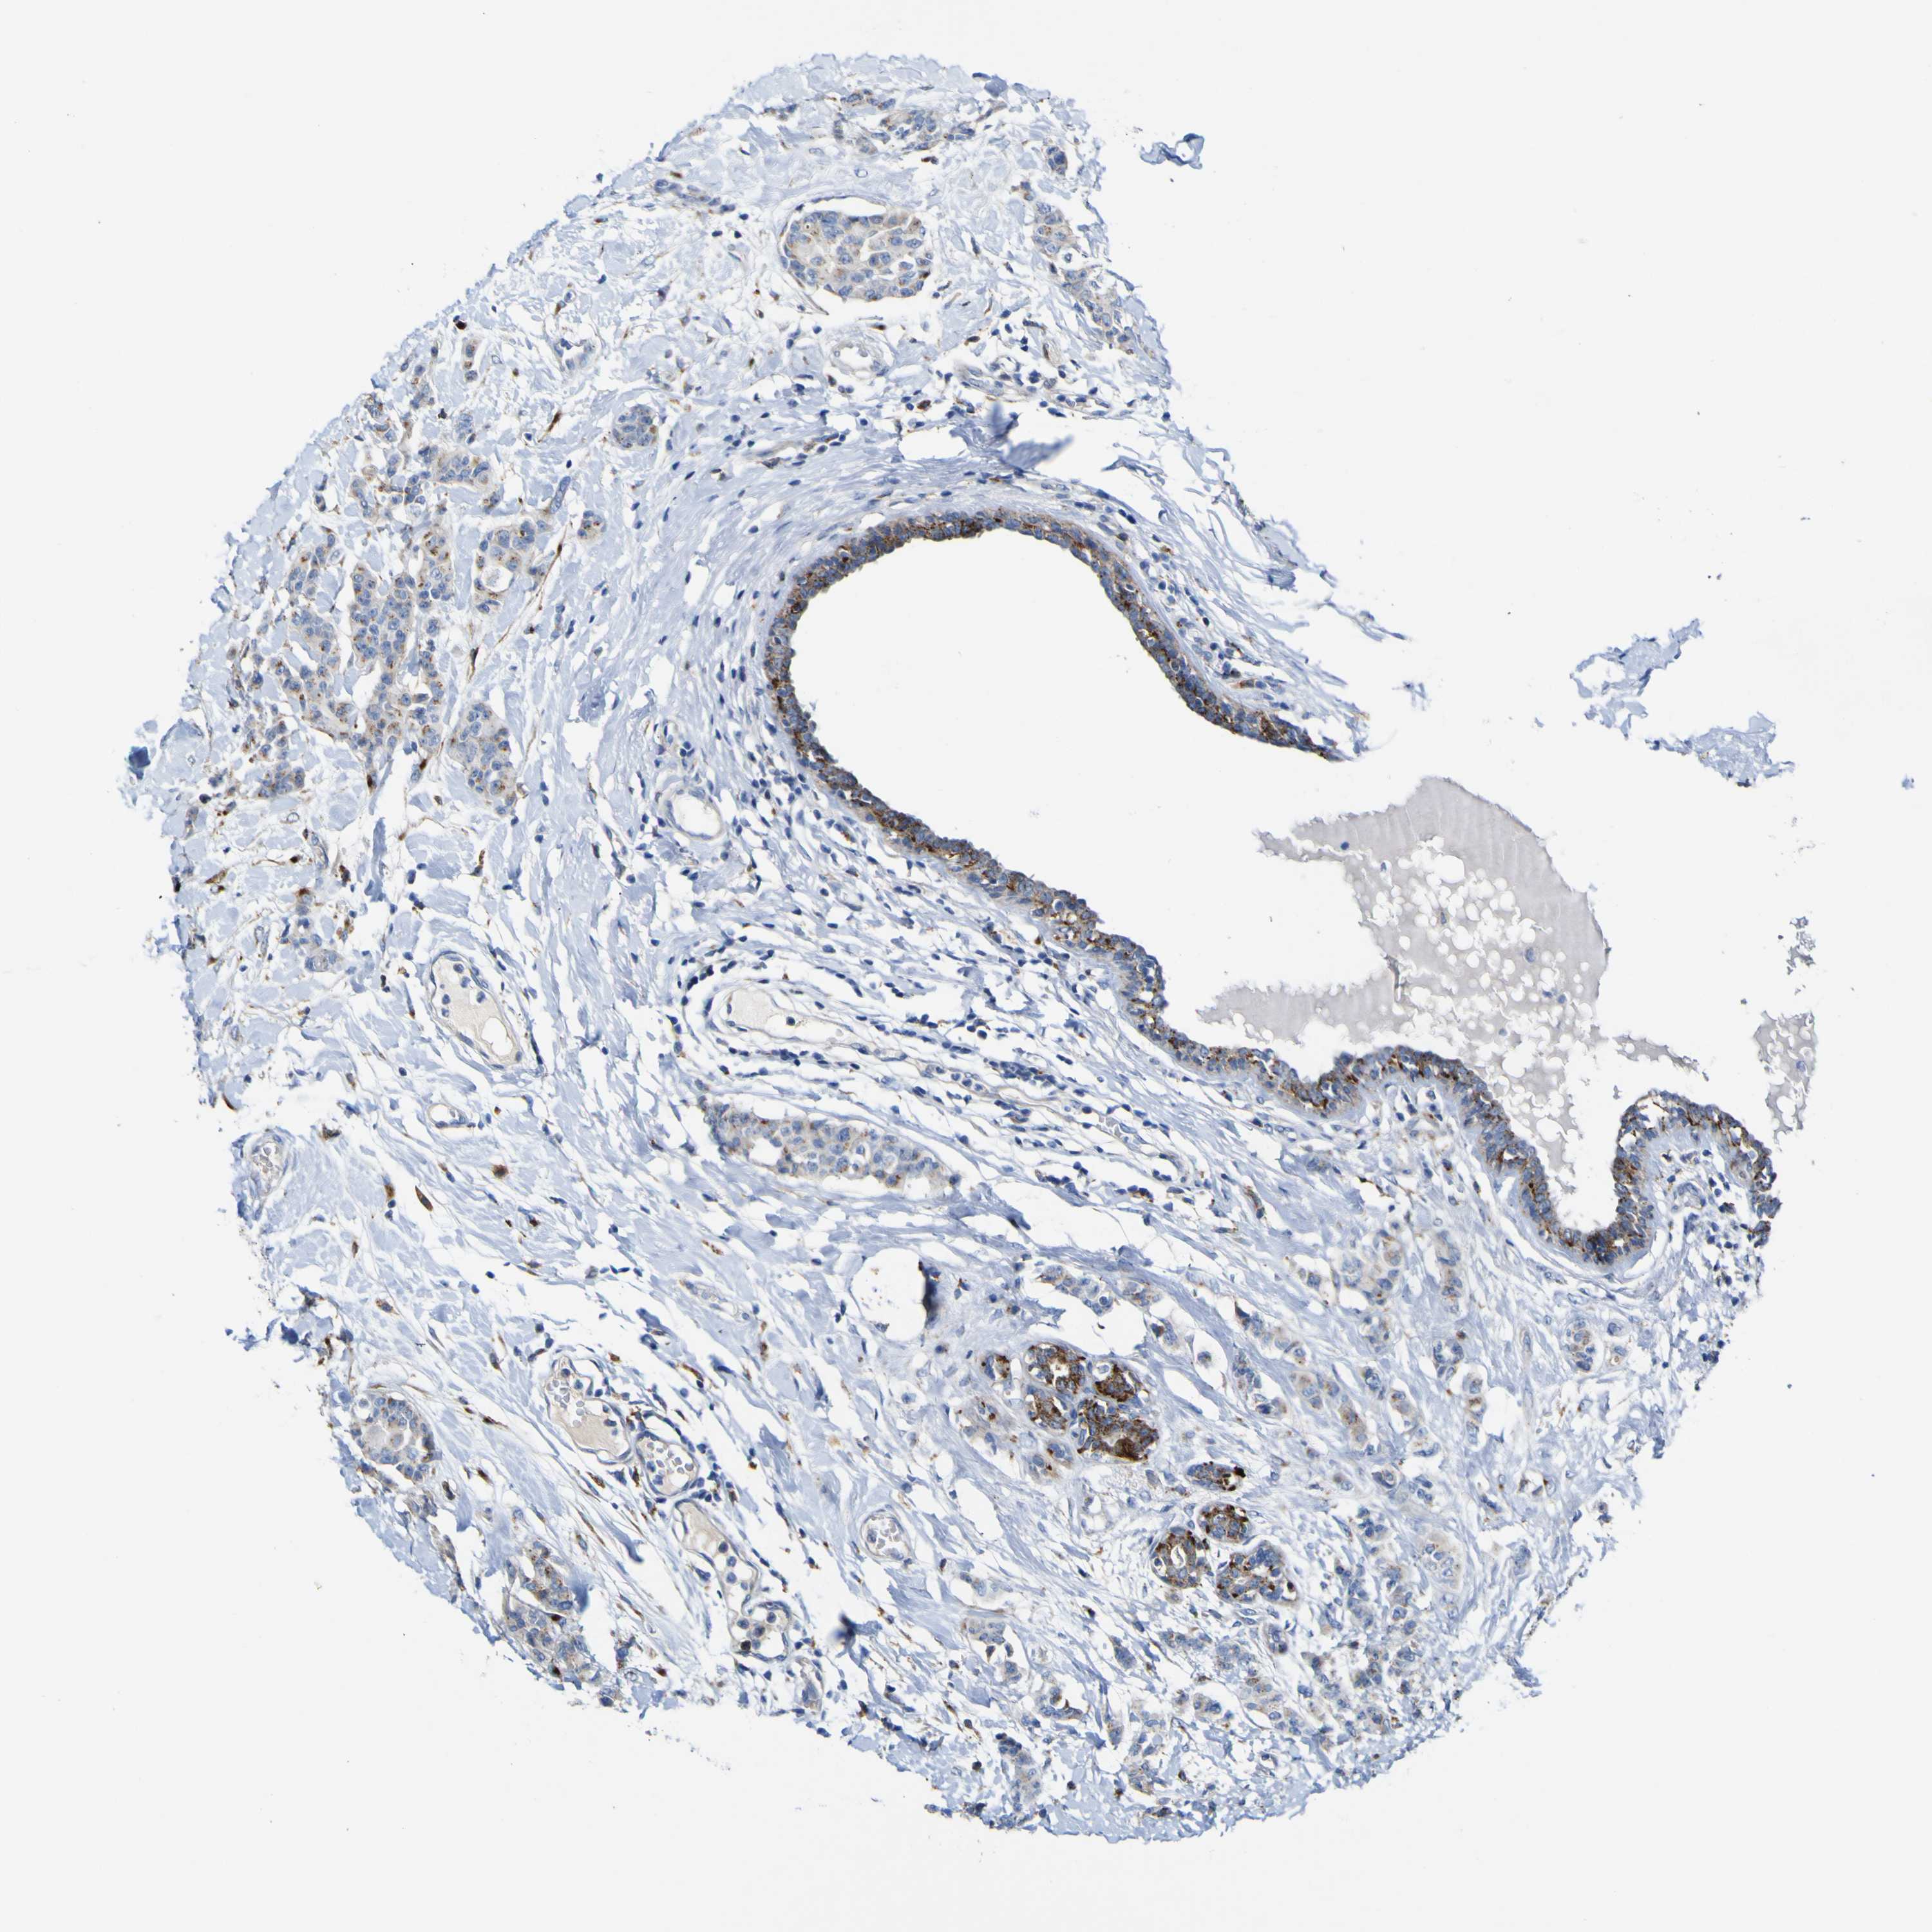

CANCER BREAST CANCER Show tissue menu

BRCA TCGA BRCA VALIDATION PROTEIN EXPRESSION

ANTIBODIES

AND

VALIDATION